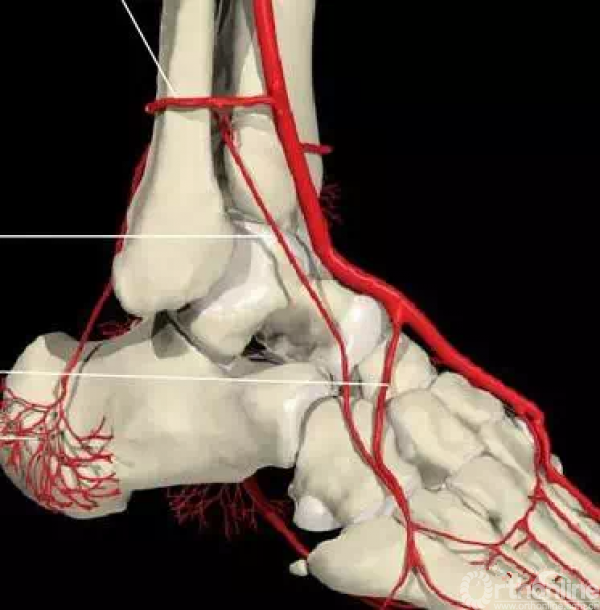

还有一个就是血供的影响,距骨很容易坏死就是血供遭到了破坏。

相关7个血管:内踝前动脉、胫后动脉、内踝支、跟骨支、跗内侧动脉、跖内侧动脉、跖外侧动脉。

最主要的血供包括:前方胫前动脉、内侧胫后动脉、外侧腓动脉的分支(跗骨窦)

当发生骨折脱位时,由于位移巨大,导致相应位移的血管损伤、最终导致距骨坏死,所以距骨骨折的分型常用Hawkins分型,距骨坏死率随分型严重程度逐渐增加。

对于是否早期手术能否减少距骨坏死仍然存在争议,有些学者认为受伤的即可就造成了血管的损伤。有些学者认为早期复位可能更有利于恢复,但是对于手术来说,减少损伤是必须的,一般只采用一侧入路,保护剩余的两处血供十分重要。